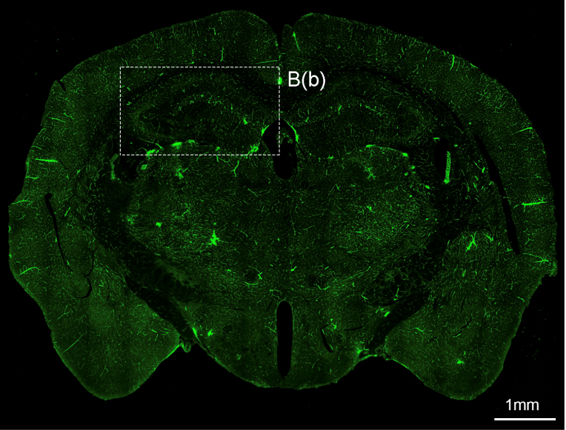

뇌혈관장애 및 퇴행성뇌질환 개선연구

- 연구주제 : 뇌혈관장애-유래 인지기능 저하 및 근감소증 제어기전 연구

- 연구주제 : 뇌경색 동물모델 구축을 통한 뇌혈관 장애 및 염증제어 후보물질 발굴